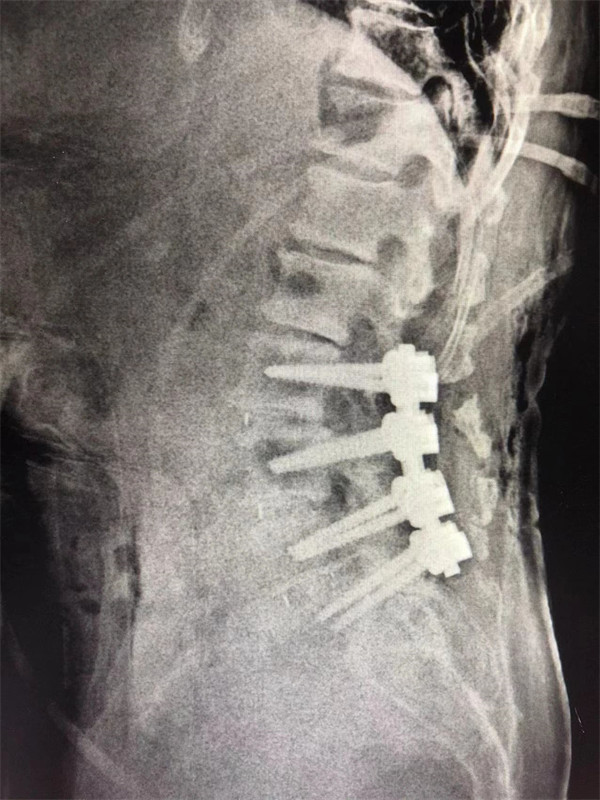

手術(shù)后↓

戈才華主任團(tuán)隊討論病情及手術(shù)風(fēng)險,并與麻醉科醫(yī)生多次討論術(shù)中麻醉風(fēng)險,經(jīng)過詳盡周密的布置之后,最終給阿婆在全麻下進(jìn)行腰3/4,4/5,腰5/骶1腰椎椎體間融合術(shù)。

術(shù)后阿婆腰痛伴雙下肢疼痛明顯緩解,術(shù)前疼得晚上睡不著覺的情況不再出現(xiàn)。阿婆和家屬連聲道謝,對醫(yī)生的治療技術(shù)和服務(wù)贊不絕口。